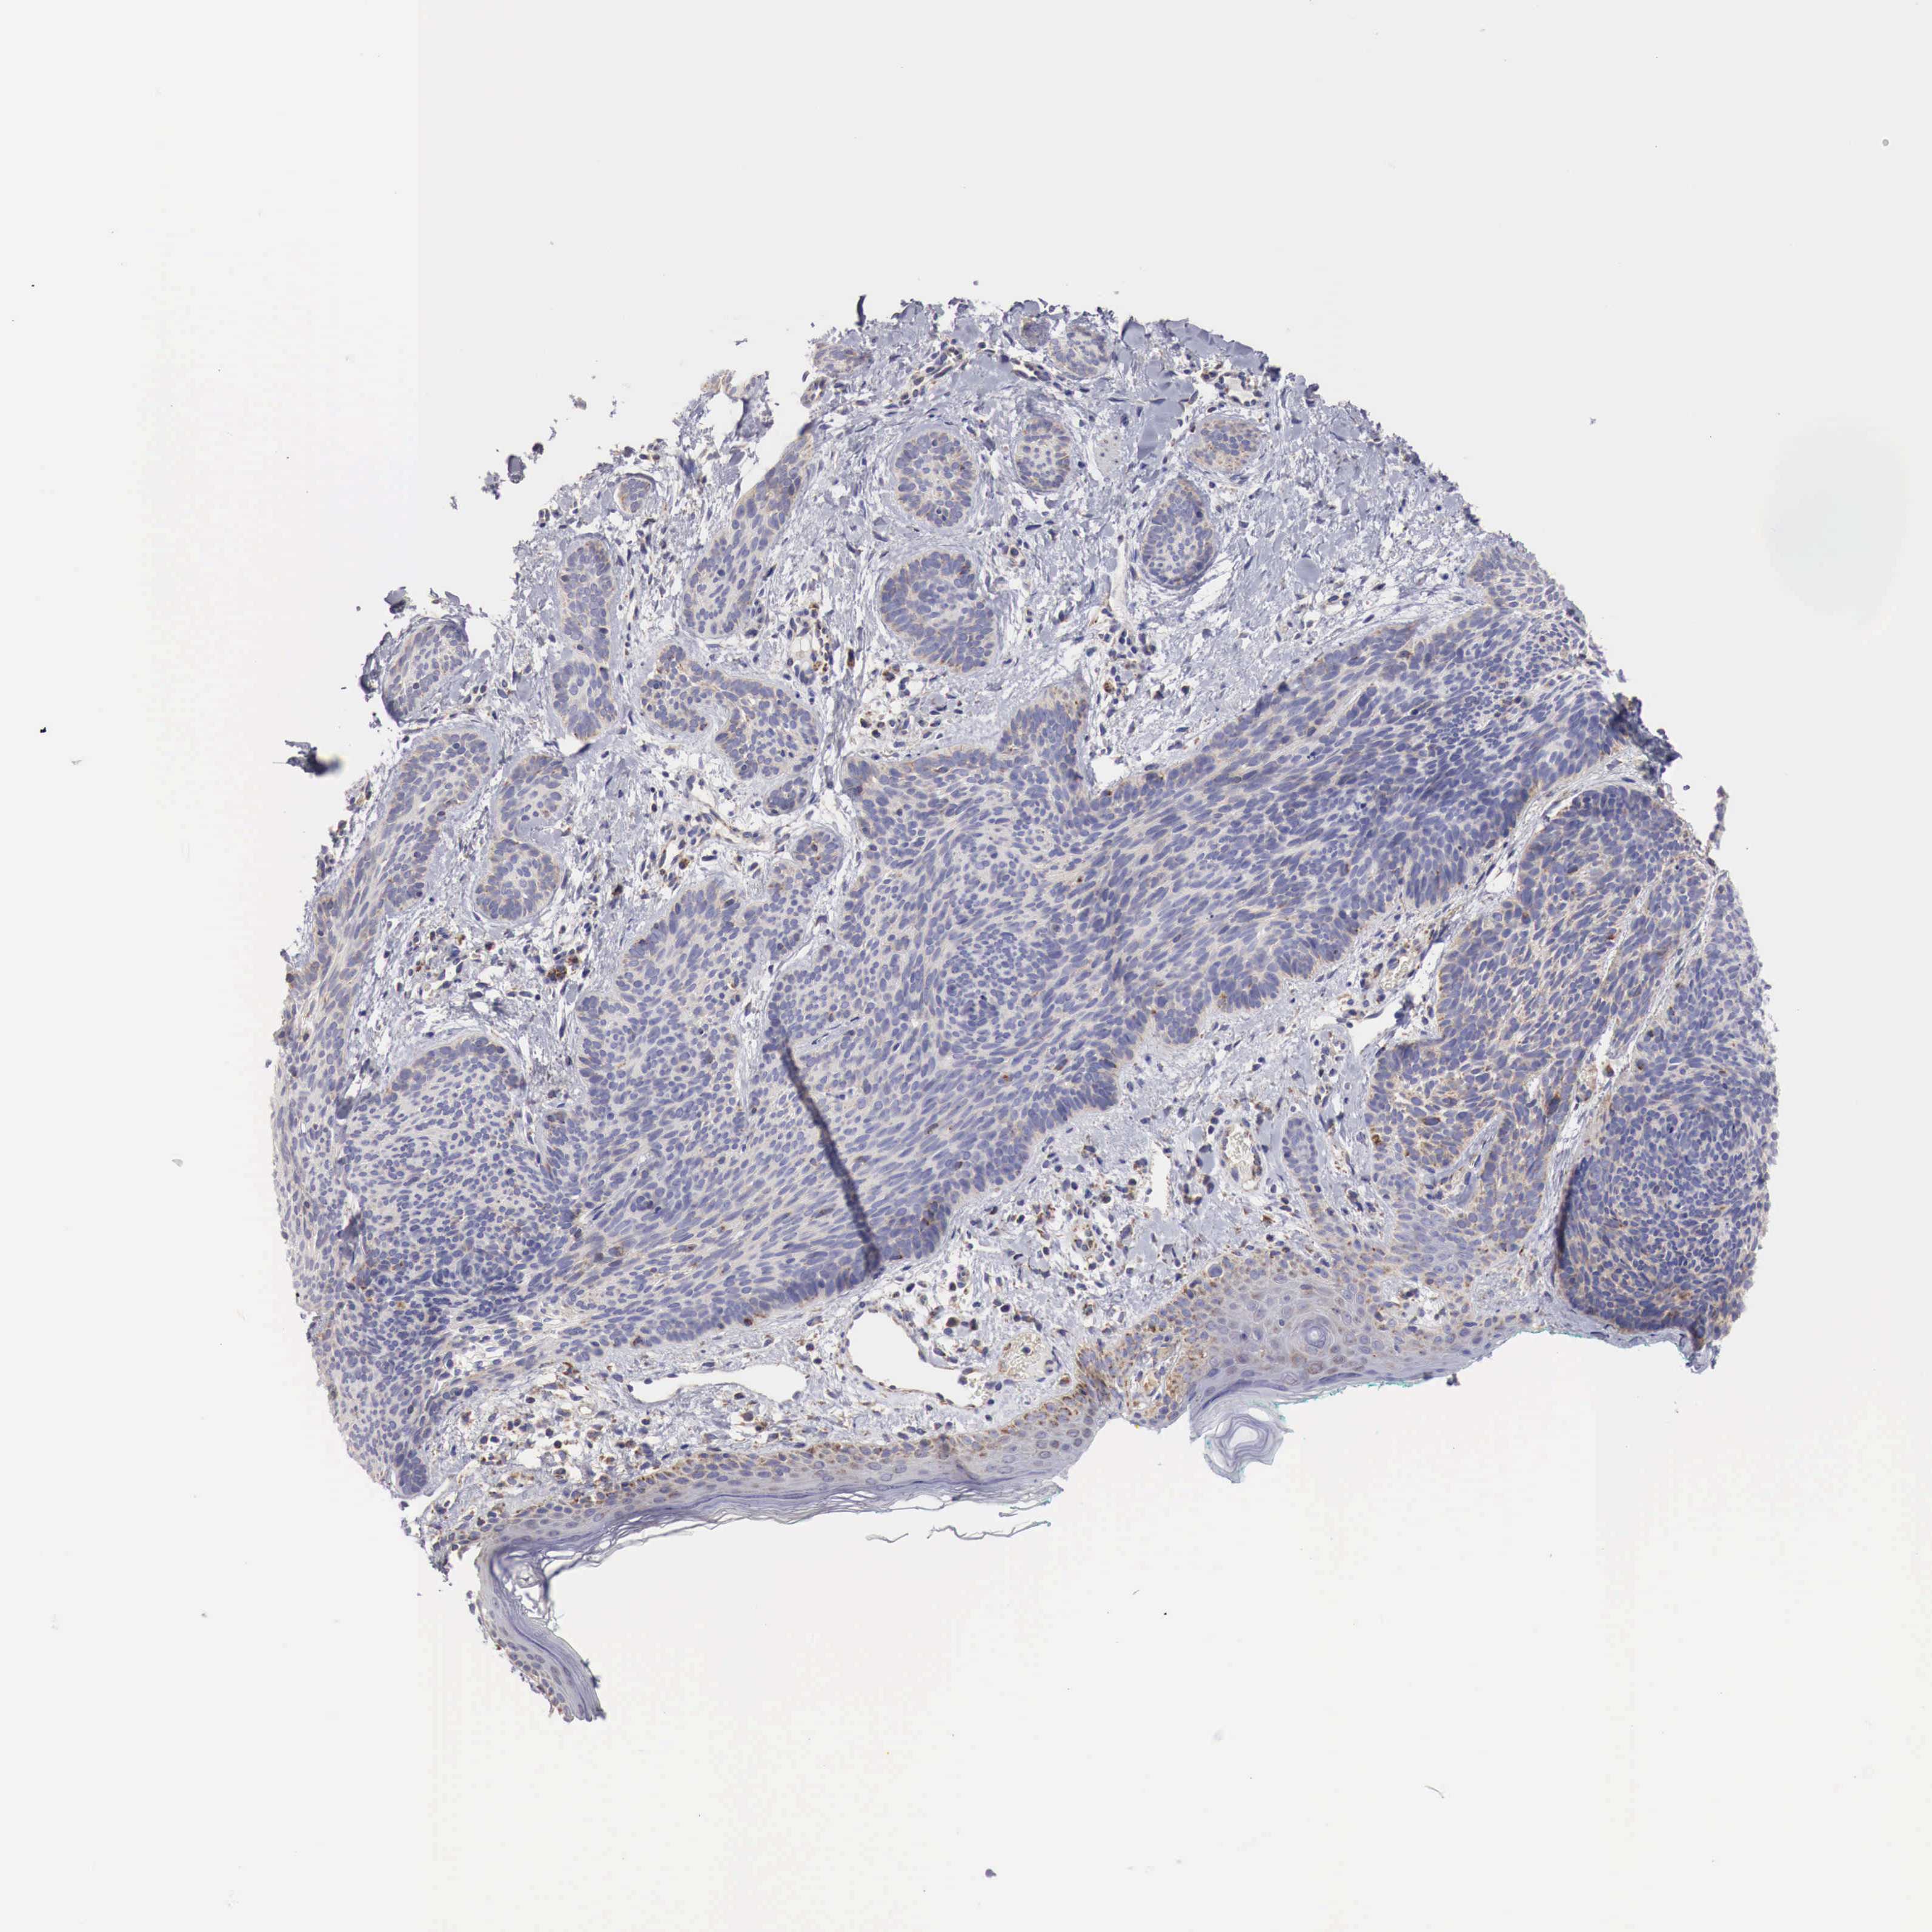

CANCER SKIN CANCER Show tissue menu

Basal cell and squamous cell cancer

SKIN CANCER - Protein expressioni

A mouse-over function shows sample information and annotation data. Click on an image to view it in a full screen mode. Samples can be filtered based on level of antibody staining by selecting one or several of the following categories: high, medium, low and not detected. The assay and annotation is described here.

Each image is clickable and will lead to virtual microscopy that enables deeper exploration of all samples and also displays staining intensity scores, fraction scores and subcellular localization as well as patient and tissue information for each sample.

Antibody HPA000527

Staining

High

Medium

Low

Not detected

Intensity

Strong

Moderate

Weak

Negative

Quantity

>75%

75%-25%

<25%

None

Location

Nuclear

Cytoplasmic/membranous

Cytoplasmic/membranous,nuclear

Squamous cell carcinoma, NOS

Basal cell carcinoma